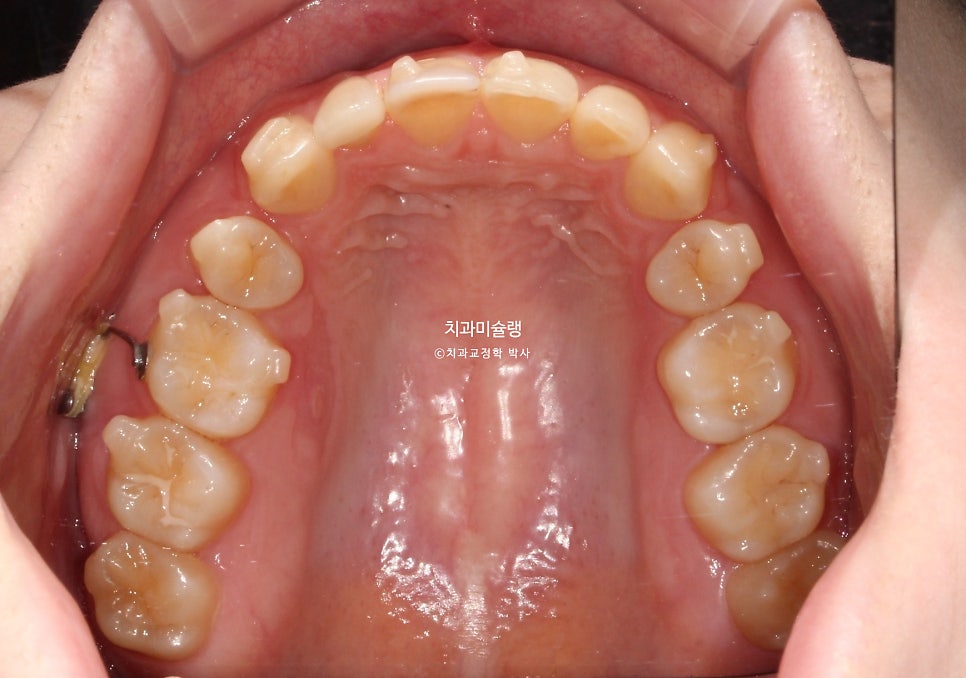

악궁이 좁고 뾰족합니다.

뽀족했던 악궁모양이 돌출된 앞니가 뒤로 들어가며 둥근 현태가 되었습니다.

작은어금니를 2개 뺐지만, 치아갯수는 14개로 정상입니다. 사랑니가 큰어금니 역할을 하고있기 때문이죠.